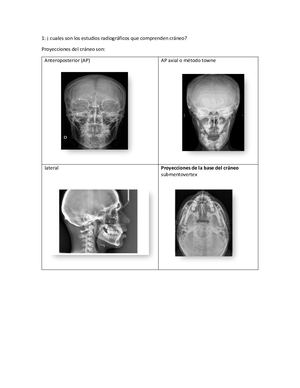

1: ¡ cuales son los estudios radiográficos que comprenden cráneo? Proyecciones del cráneo son: Anteroposterior (AP) AP axial o método towne lateral Proyecciones de la base del cráneo submentovertex